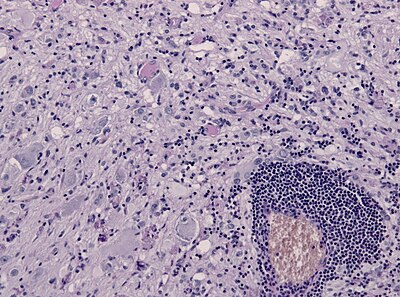

2

Diagnosis?

Myxopapillary ependymoma-HE.jpg

Pilocytic astrocytoma

Diffuse Astrocytoma

Pleomorphic xanthoastrocytoma

Subependymal giant cell astrocytoma

Oligodendroglioma

Glioblastoma, classic

Glioblastoma, epitheloid

Giant cell glioblastoma

Gliosarcoma

Ependymoma

Subependymoma

Myxopapillary ependymoma

Ganglioglioma

Choroid plexus papilloma

Angiocentric glioma

Dysembryoplastic neuroepithelial tumour

Neurocytoma

Paraganglioma

Pineocytoma

Papillary glioneuronal tumour

Medulloblastoma

CNS PNET